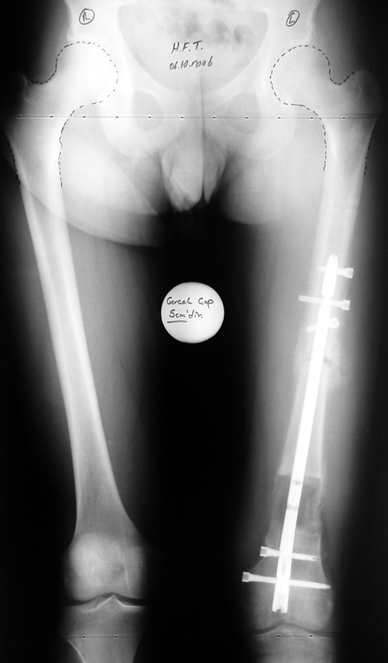

3. POSTTRAUMATIC LOWER LIMB SHORTNESS (MALUNION)

This type of shortness occurs after a fracture heals in a shortened position. Most cases are seen in adults and can be treated with one lengthening operation. Additional deformities can be corrected simultaneously. Most of these cases can be treated with lengthening over nail or just corrections and intramedullary nailing.